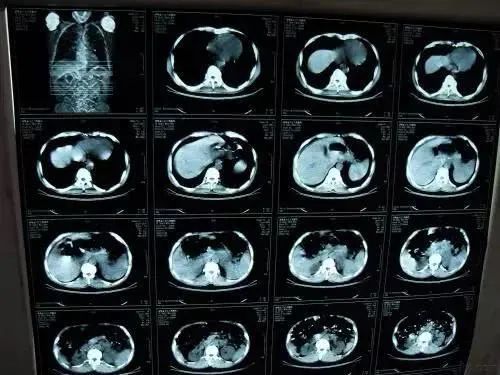

肺癌恶性肿瘤图片

肺癌恶性肿瘤图片,良性与恶性肿瘤图片

其肺部的支气管黏膜部位出现恶性肿瘤,并且肺癌的发病率以及死亡率也

肺癌是最常见的恶性肿瘤之一,发病率,死亡率都高居全部肿瘤疾病之首.

早期肺癌无处遁身—低剂量肺部ct筛查

发现他的肺部已经长满了恶性肿瘤,是晚期肺癌

肺部恶性肿瘤ct图片

肺癌ct图片